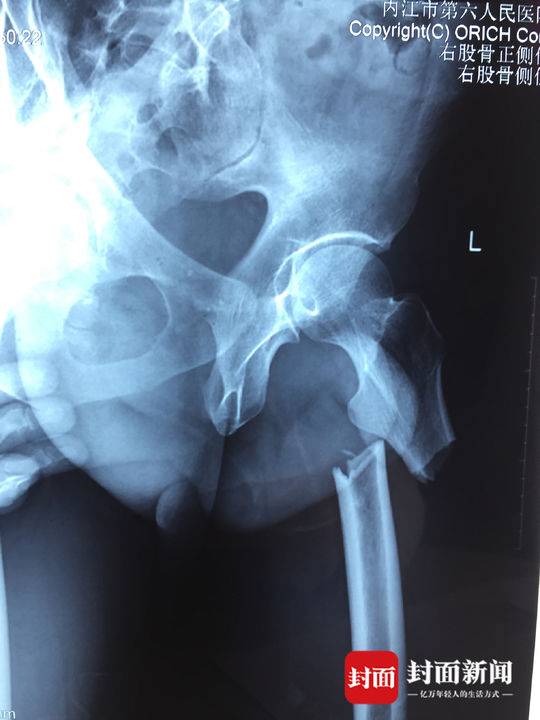

“刚开始恼火得很!他躺在病床上,身都不能翻一下。”隔壁病床的陈洪富说,邓强刚进医院时脸色苍白,情况看上去很糟糕。经过医院检查,邓强的左腿股骨上段骨折,导致整条腿都不能动。“家里负担重,不知道以后还能不能上工地挣钱。”邓强的家庭条件并不好。